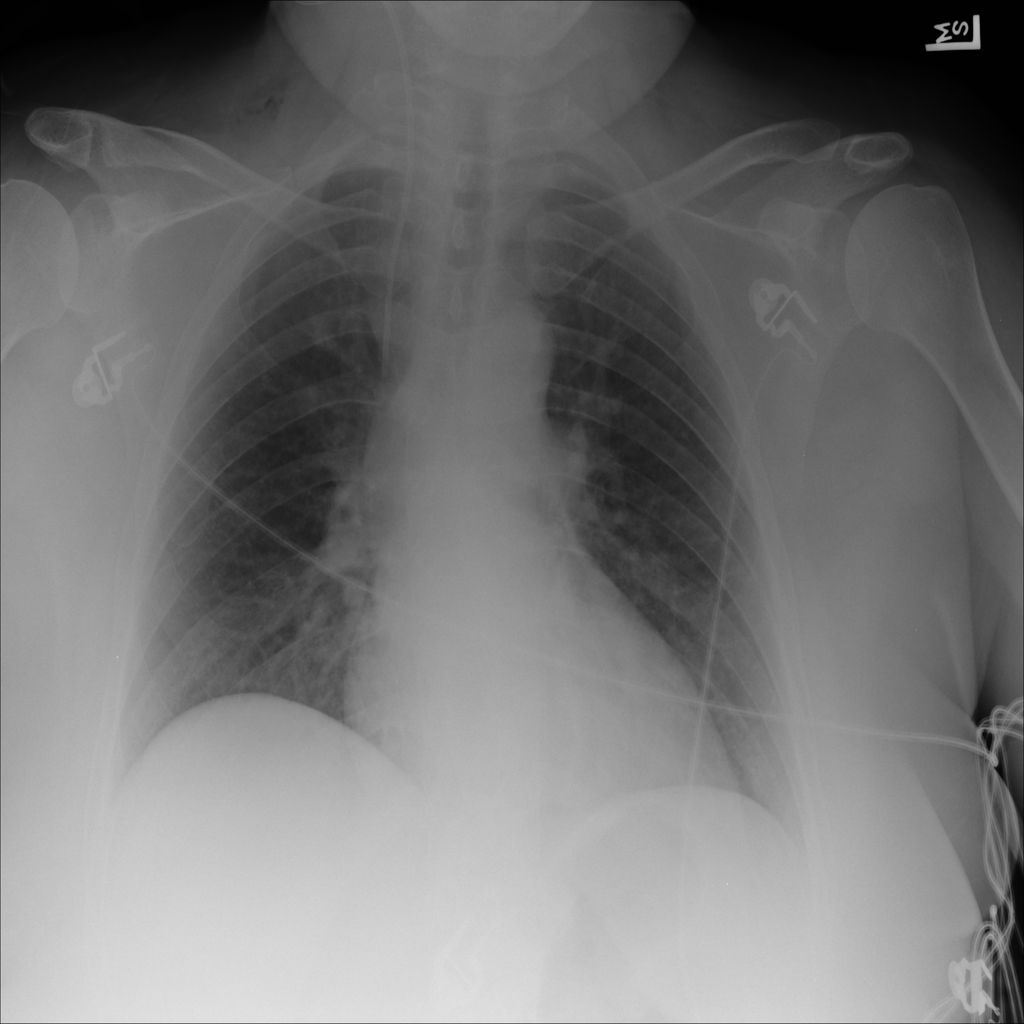

Showing up to 90 reference images for Emphysema.

PAT-ED3E · IMG-002Emphysema

PAT-ED3E · IMG-002

AP